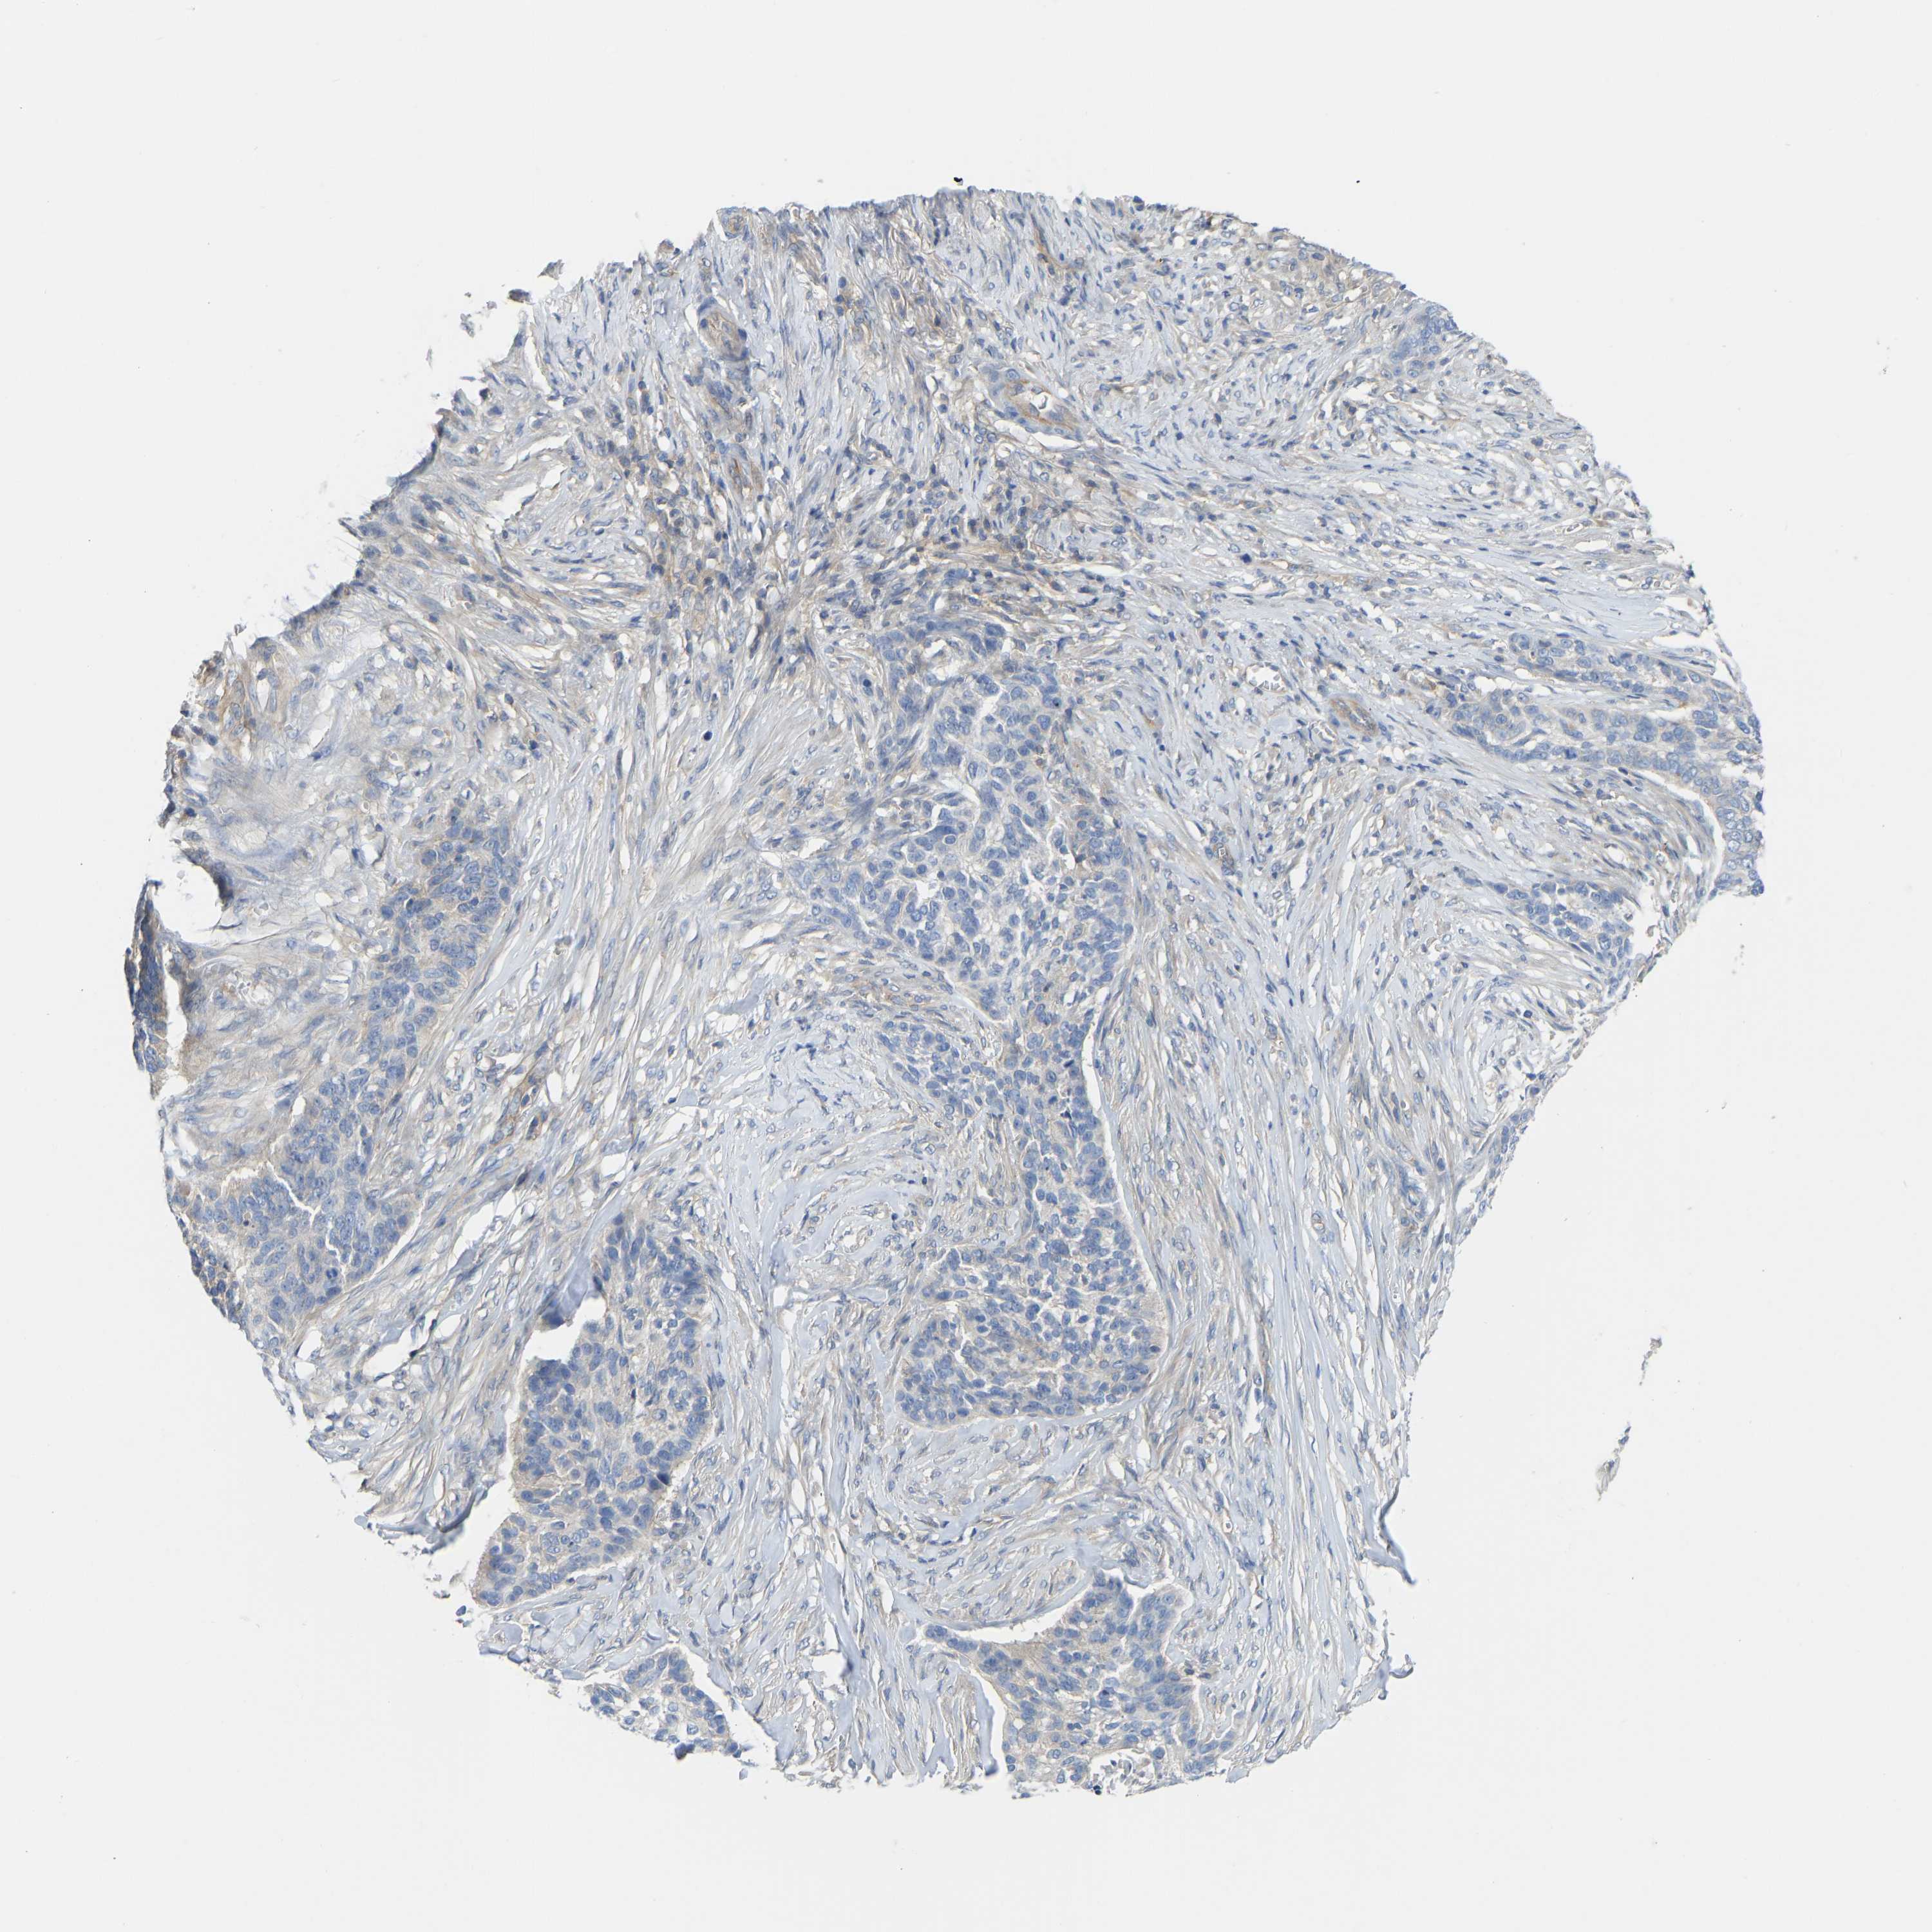

SKIN CANCER - Protein expressioni

A mouse-over function shows sample information and annotation data. Click on an image to view it in a full screen mode. Samples can be filtered based on level of antibody staining by selecting one or several of the following categories: high, medium, low and not detected. The assay and annotation is described here.

Antibody stainingi

Antibody staining in the annotated cell types in the current human tissue is reported as not detected, low, medium, or high, based on conventional immunohistochemistry profiling in selected tissues. This score is based on the combination of the staining intensity and fraction of stained cells.

Each image is clickable and will lead to virtual microscopy that enables deeper exploration of all samples and also displays staining intensity scores, fraction scores and subcellular localization as well as patient and tissue information for each sample.

Antibody HPA012778

Basal cell carcinoma